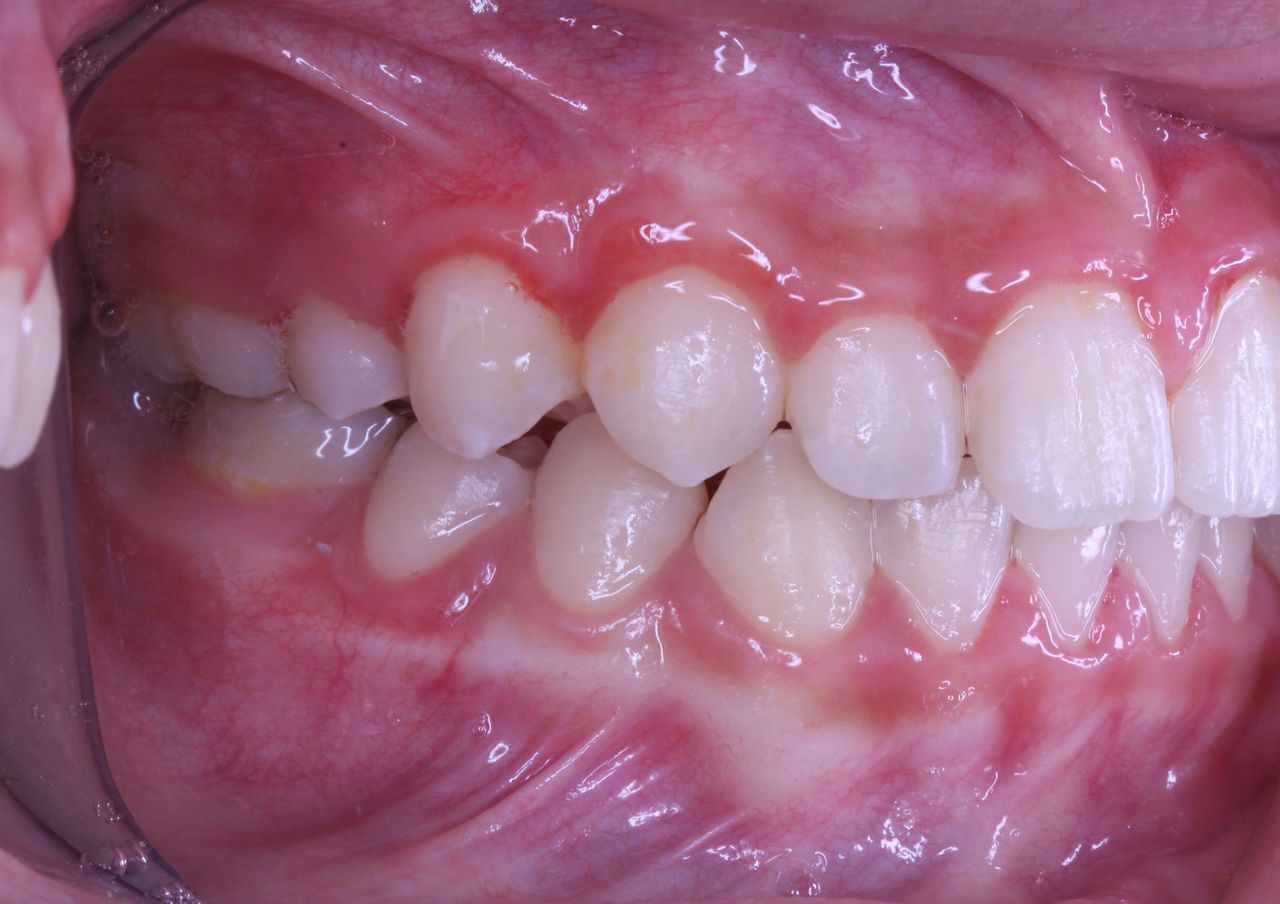

横から生えてきた永久歯も向きは悪いですが、かなり良い方向に降りてきました。

一方で出てきたときの状況は

現在の状況です

中学2年生になりました。

上顎も下顎もそこそこの歯列になっていると思います。

咬み合わせも良好です

なんと、大人の歯は虫歯0本で管理されてます!